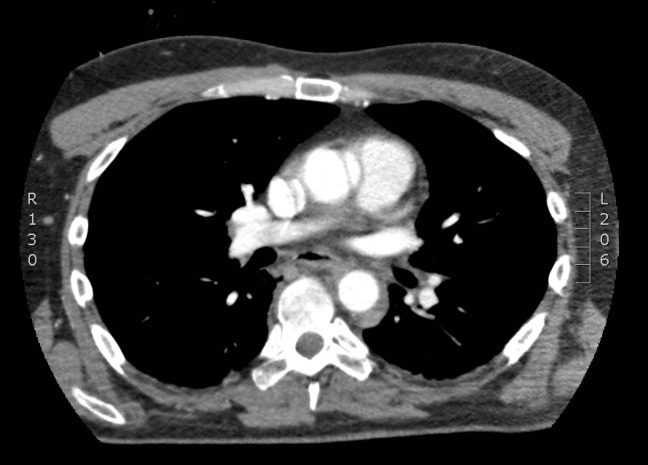

Case presentation: A 36-year-old male was transferred following a fire suppressant explosion at a copper smelter. He presented with central chest pain and stable hemodynamics, with no signs of external chest trauma. Computed tomography (CT) imaging revealed a localized dissection of the ascending aorta and a partial rupture of the aortic arch, in addition to fractures in the hand and foot caused by suppressant debris. The patient subsequently became hemodynamically unstable and required urgent surgical intervention. He underwent ascending aortic and aortic arch repairs. Postoperatively, his course was complicated by a pulmonary embolism, which was managed medically. He was eventually discharged after recovering from his injuries.